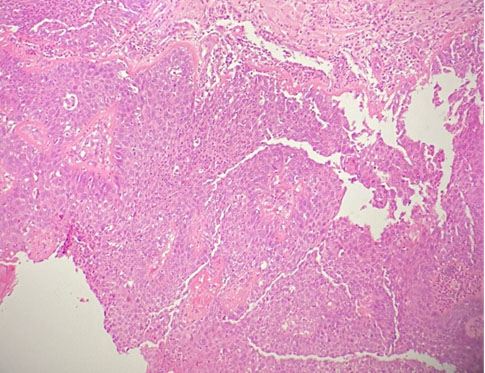

Components of mature epidermis, skin appendages, adipose tissue, cartilaginous tissue, respiratory type epithelium were seen. In areas, aggregates of histiocytes and multinucleated giant cells were found. There was a focus (4 mm) of trabecular pattern of cells with oval nuclei and eosinophilic cytoplasm (Figure 7). These cells were immunoreactive to synaptophysin, in keeping with a carcinoid component.

At some areas, the fibrous cyst wall and focal broad papillary structures were lined by thickened stratified squamous epithelium with loss of maturation, marked nuclear pleomorphism, occasional prominent nucleoli, and readily seen mitotic figures. There was no definite stromal invasion despite examination of multiple levels. No immature neuroepithelium or other immature element was seen. Features were those of squamous cell carcinoma in situ and carcinoid tumor arising from a mature cystic teratoma (Figure 8).

Figure 7: Case 2 carcinoid tumor under low power field, × 100. There is a focus (4 mm) of trabecular pattern of cells with oval nuclei and eosinophilic cytoplasm.

Figure 8: Case 2 tumor with squamous cell carcinoma in situ under low power field, × 100. The fibrous cyst wall and focal broad papillary structures are lined by thickened stratified squamous epithelium with loss of maturation, marked nuclear pleomorphism, occasional prominent nucleoli, and readily seen mitotic figures. There is no definite stromal invasion.